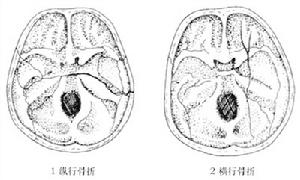

(2)貫通傷:有入口和出口,入口小,出口大。顱內入口及顱外皮下出口附近有碎骨片,腦挫裂傷嚴重,若傷及生命中樞,傷員多在短時間內死亡。

(3)切線傷:頭皮、顱骨和腦呈溝槽狀損傷或缺損,碎骨片多在顱內或顱外。